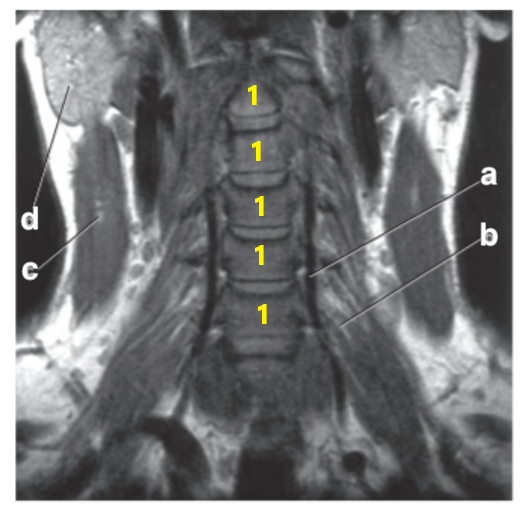

What imaging plane is this?

coronal

What is letter f?

Cervical Spinal cord